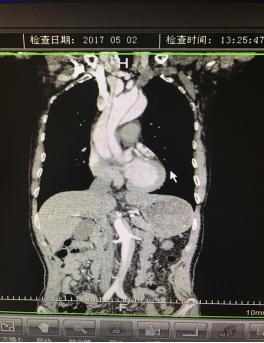

5月2號劉大伯照常早起干活,突然胸部劇烈疼痛,難以忍受,全身大汗,同時伴有右上肢發(fā)涼,他心想這次心絞痛比之前嚴重的多啊,趕緊叫上孩子到吉林國文醫(yī)院心血管內(nèi)科住院,患者長期高血壓病史,血壓一直控制不理想,大夫給他做了檢查,測左上肢血壓:82/45mmHg,右上肢血壓測不出,心率52次/分,右側(cè)肱動脈、尺動脈、橈動脈搏動消失,左側(cè)股動脈搏動較右側(cè)弱?!霸懔耍p側(cè)血壓差別這么大,是不是主動脈夾層了?”,接診大夫趕緊找來李主任,李主任反復(fù)詢問患者病情,表情突然凝重起來,患者胸痛這么明顯,血壓低的厲害,主動脈夾層的可能性很大。二話不說,李主任立即聯(lián)系影像科的醫(yī)生準備做主動脈CTA,移動患者做檢查的過程大夫們非常小心,嚴密監(jiān)測患者血壓變化情況。兩個小時后結(jié)果出來了,主動脈夾層從升主動脈一直撕裂到左側(cè)髂總動脈?。?!

從開始學醫(yī)到現(xiàn)在已經(jīng)快9年了,主動脈夾層患者也見過一些,但像劉大伯這種危險類型的還是第一次見到,心里真的為他捏把汗,撕裂的主動脈隨時都有可能破裂,生命隨時可能終止,要知道主動脈夾層的死亡率非常的高,約50%的患者發(fā)病后48小時死亡,約90%的患者發(fā)病1個月內(nèi)死亡。